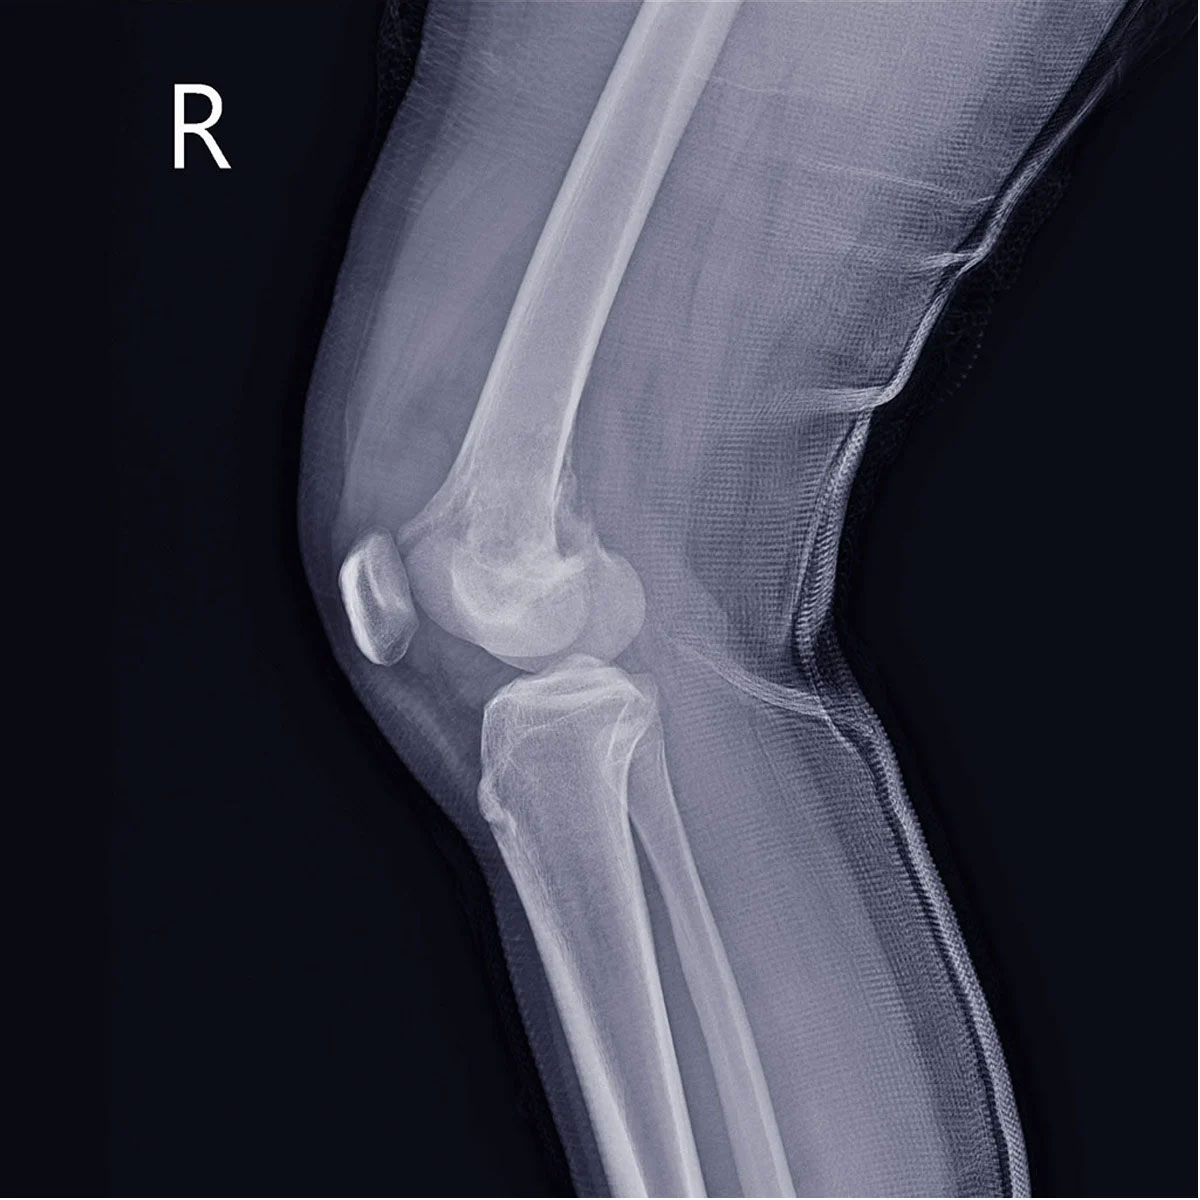

- Рентгенографія є первинним і найдоступнішим методом діагностики хондросаркоми. На рентгенівських знімках центральні хондросаркоми зазвичай виглядають як вогнища деструкції неправильної форми з нечіткими контурами, які часто розташовані в метадіафізі кістки. Характерною ознакою є крапчастий вигляд пухлини через дрібні вогнища обвапнення. Також помітне здуття кістки навколо ураженої ділянки. Периферичні хондросаркоми, у свою чергу, виявляються як контрастне утворення горбкуватої форми, розташоване на зовнішній поверхні кістки.